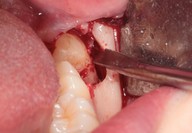

Galleria fotografica